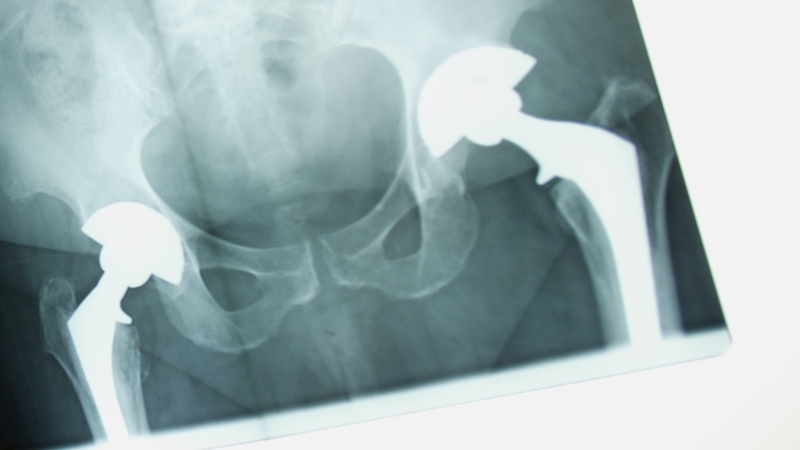

Some Irish patients who have undergone a hip replacement face the possibility of surgery to replace the device after revelations that a faulty product may have been used.

The recall involves the DePuy ASR AX acetabular system launched in 2004. It is distributed in Ireland by PEI.

Problems associated with the device include loosening parts, infections, fractures, dislocation, sensitivity to the metal and pain.

Corrective surgery is more complicated and costly than primary surgery as surgeons have less bone and more scar tissue to work with.